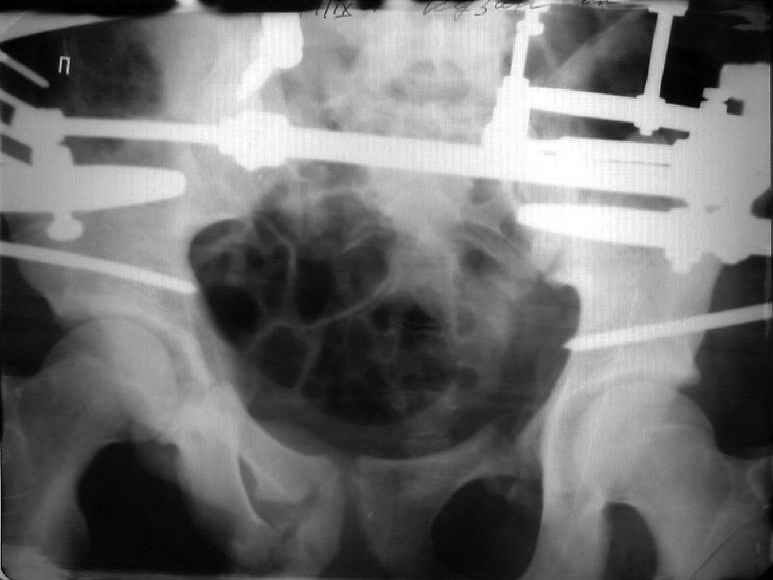

Застарелый перелом таза

Уважаемые коллеги! Хотел-бы обсудить варианты лечения больной с застарелым переломом таза. Возраст 40 лет. Травма 11 месяцев назад. Главный травматолог Камчатского Военно-морского госпиталя Юрий Алексеевич Булахтин

У больного судя по всему вертикальная деформация таза. А каковы основные жалобы пациента и какие у него функциональные требования?

Для информации к размышлению о возможности исправления имеющейся деформации предлагаю похожий случай.